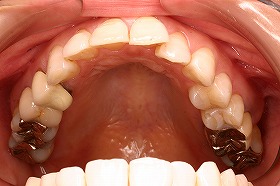

ガタガタの歯並びだと歯と歯のすき間に

ハミガキが行き届かず歯石が残り易くなります。

その歯石が虫歯や歯槽膿漏などの原因となり、

歯に悪影響を及ぼすのです。